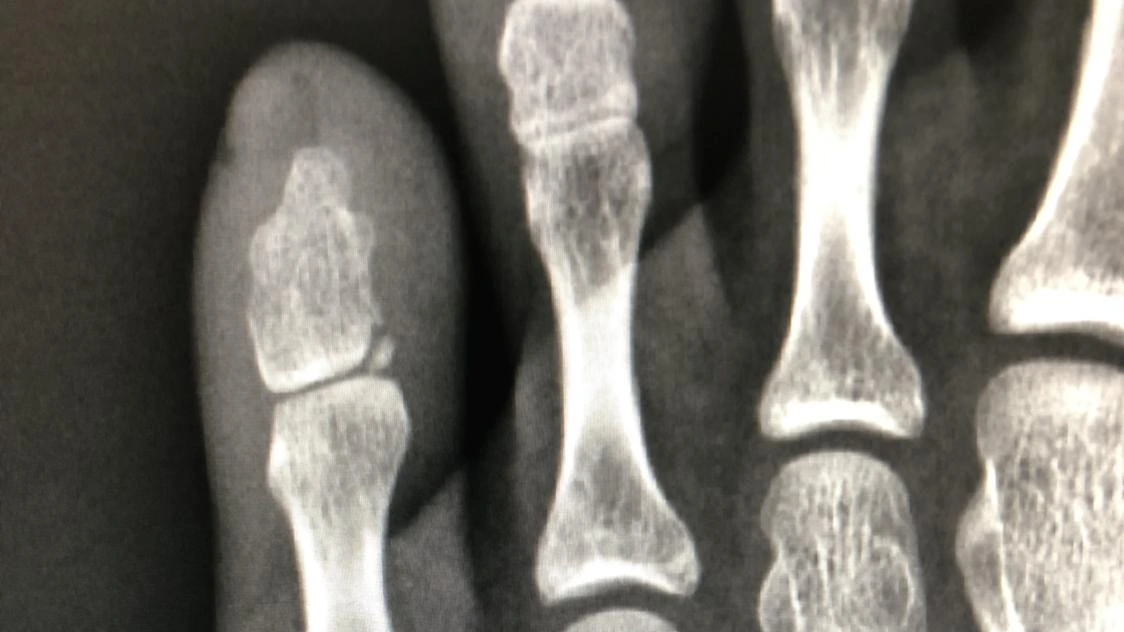

사진을 하나하나 넘겨 보다가 촬영실 주인이 찍어준 엑스레이 사진을 발견했다. 대체 어디가 브로큰이라는 거야? 무심코 사진을 확대하다가 벌-떡! 일어섰다. 댕, 얻어 맞은 느낌.

"나.. 브로큰 된 거 맞나 봐.."

새끼발가락에 작은 뼈 조각이...

선명하게 떨어져 나간 조각이...

보였다.

촬영실 주인이 네일아트한 손톱으로 짚어 보이던 바로 그 위치에.